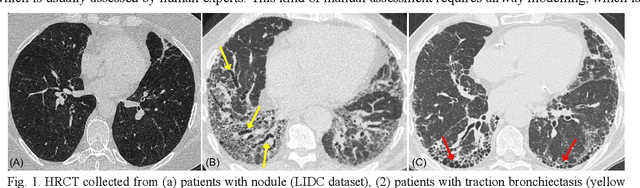

Abstract:Airway-related quantitative imaging biomarkers are crucial for examination, diagnosis, and prognosis in pulmonary diseases. However, the manual delineation of airway trees remains prohibitively time-consuming. While significant efforts have been made towards enhancing airway modelling, current public-available datasets concentrate on lung diseases with moderate morphological variations. The intricate honeycombing patterns present in the lung tissues of fibrotic lung disease patients exacerbate the challenges, often leading to various prediction errors. To address this issue, the 'Airway-Informed Quantitative CT Imaging Biomarker for Fibrotic Lung Disease 2023' (AIIB23) competition was organized in conjunction with the official 2023 International Conference on Medical Image Computing and Computer Assisted Intervention (MICCAI). The airway structures were meticulously annotated by three experienced radiologists. Competitors were encouraged to develop automatic airway segmentation models with high robustness and generalization abilities, followed by exploring the most correlated QIB of mortality prediction. A training set of 120 high-resolution computerised tomography (HRCT) scans were publicly released with expert annotations and mortality status. The online validation set incorporated 52 HRCT scans from patients with fibrotic lung disease and the offline test set included 140 cases from fibrosis and COVID-19 patients. The results have shown that the capacity of extracting airway trees from patients with fibrotic lung disease could be enhanced by introducing voxel-wise weighted general union loss and continuity loss. In addition to the competitive image biomarkers for prognosis, a strong airway-derived biomarker (Hazard ratio>1.5, p<0.0001) was revealed for survival prognostication compared with existing clinical measurements, clinician assessment and AI-based biomarkers.